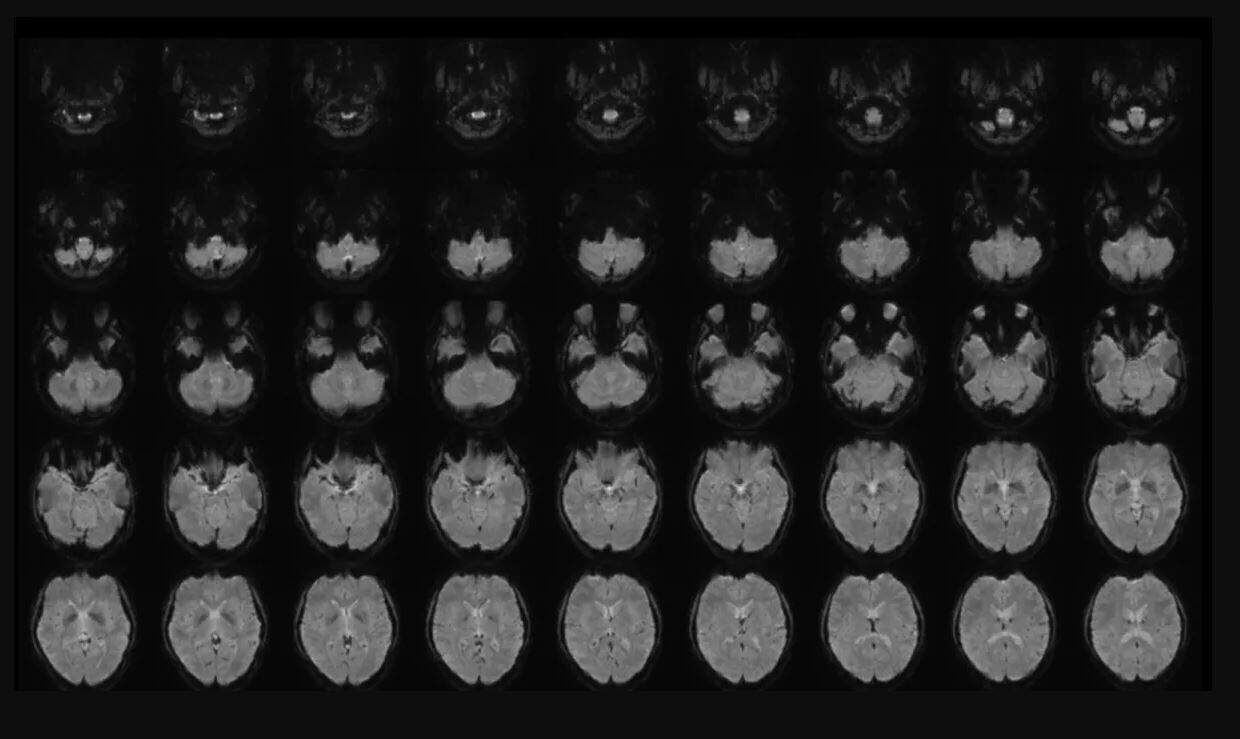

Ressonância magnética do cérebro ajudou cientista a interpretar pensamentos e criar frases a partir deles. (Foto: Divulgação)